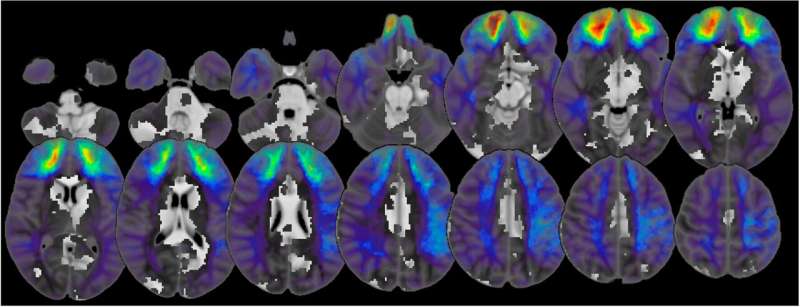

“Biz ise lezyon ağ haritalama (lesion network mapping) adı verilen daha yeni bir teknik kullandık. Bu yöntem, insan beyninin bölgeleri arasındaki bağlantıları gösteren büyük ölçekli bir harita olan insan konektomuna dayanıyor. Konektom, beynin işlevsel ve yapısal bağlantılarını bir ağ gibi gösteriyor. Bu sayede, beynin farklı bölgelerinde bulunan ancak aynı sinirsel devreyi etkileyen lezyonları birbirine bağlayabiliyoruz.”

Bu deneysel yöntemleri kullanarak, araştırmacılar siyasi davranışa katkıda bulunan ve tekrarlanabilir nitelikte bir beyin devresini ortaya çıkardı. Bu devrenin, kişilerin siyasi görüşlerini (örneğin liberal ya da muhafazakâr olmalarını) etkilemekten çok, siyasi davranışlarının yoğunluğunu düzenlediği tespit edildi.